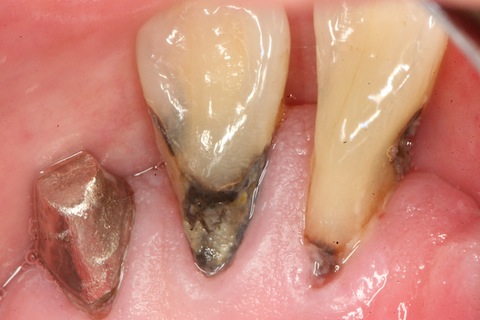

CR充填後